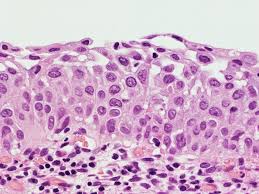

9b Normal Cytology And Benign Reactive Changes Eurocytology from www.eurocytology.eu The transformation zone of the cervix (where columnar and squamous cells meet) is in a continuous process of repair, and squamous metaplasia and inflammation may block a gland orifice. The endocervical columnar cells continue to secrete but are covered by squamous epithelium, forming a mucinous retention cyst. The cervix or cervix uteri (latin, 'neck of the uterus') is the lower part of the uterus in the human female reproductive system.the cervix is usually 2 to 3 cm long (~1 inch) and roughly cylindrical in shape, which changes during pregnancy. In premenopausal women, the transformation zone is fully located on the ectocervix. Edited by frappart l, fontaniere b, lucas e, sankaranarayanan r. In order to visualize koilocytes collected from the cervix, the tissue is stained with the papanicolaou stain. It corresponds to the area of cervix bound by the original squamocolumnar junction at the distal end and proximally by the furthest extent that squamous metaplasia has occurred as defined by the new squamocolumnar junction. Immature squamous metaplasia (see comment)

Because hpv has a predilection for this region, 14 screening must focus on sampling the cells at the transformation zone to adequately detect the presence of dysplasia. In order to visualize koilocytes collected from the cervix, the tissue is stained with the papanicolaou stain. The transformation zone of the cervix (where columnar and squamous cells meet) is in a continuous process of repair, and squamous metaplasia and inflammation may block a gland orifice. Immature squamous metaplasia (see comment) The endocervical columnar cells continue to secrete but are covered by squamous epithelium, forming a mucinous retention cyst. Squamous metaplasia transitional (urothelial) metaplasia tuboendometrioid metaplasia inflammatory / infectious: May 31, 2018 · the transformation zone of the cervix is the region where squamous epithelium replaces glandular epithelium in a process called squamous metaplasia. It corresponds to the area of cervix bound by the original squamocolumnar junction at the distal end and proximally by the furthest extent that squamous metaplasia has occurred as defined by the new squamocolumnar junction. In premenopausal women, the transformation zone is fully located on the ectocervix. It corresponds to the area of cervix bound by the original squamocolumnar junction at the distal end and proximally by the furthest extent that squamous metaplasia has occurred as defined by the new squamocolumnar junction. In premenopausal women, the transformation zone is fully located on the ectocervix. The cervix or cervix uteri (latin, 'neck of the uterus') is the lower part of the uterus in the human female reproductive system.the cervix is usually 2 to 3 cm long (~1 inch) and roughly cylindrical in shape, which changes during pregnancy. Edited by frappart l, fontaniere b, lucas e, sankaranarayanan r.

Edited by frappart l, fontaniere b, lucas e, sankaranarayanan r. Squamous metaplasia transitional (urothelial) metaplasia tuboendometrioid metaplasia inflammatory / infectious: Immature squamous metaplasia (see comment) May 31, 2018 · the transformation zone of the cervix is the region where squamous epithelium replaces glandular epithelium in a process called squamous metaplasia. Because hpv has a predilection for this region, 14 screening must focus on sampling the cells at the transformation zone to adequately detect the presence of dysplasia.